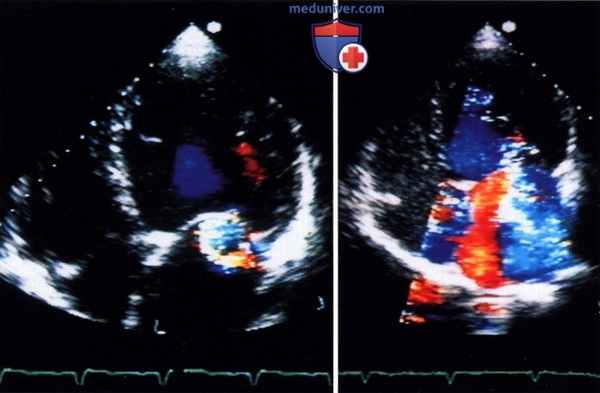

а) Недостаточное выявление потоков из-за проблем с чувствительностью. Многие записи цветовой допплер-ЭхоКГ из апикального доступа не содержат вообще или содержат довольно малоцветокодированной информации в области предсердий. Такое положение дел должно бы вызвать у исследователя критическое отношение к правдивости получаемой информации о потоках крови.

В действительности ультразвуковая картинка по правильности воспроизведения никогда не сможет конкурировать с цветными фотографиями, ибо она есть и остается лишь конструкцией грамотных инженеров, перенесших феномены из области акустики сначала в изменения электрических потенциалов, а затем - в область оптики для построения изображения. Таким образом, представленная информация является высокоселективной. Но то, что при этом не представлено (чаще всего это связано с техническими ограничениями), может быть настолько важным, что отсутствие этих данных на экране в конечном итоге приведет к неверной информации.

Пример неверной информации. На рисунке ниже слева показан подобный пример, создающий у исследователя впечатление, что у этого пациента с митральной недостаточностью во время систолы в области левого предсердия нет никакого антеградного потока. Однако кардиологу даже с умеренным знанием основных гемодинамических закономерностей известно, что в систолу и раннюю диастолу предсердия интенсивно наполняются из легочных вен и что при неискаженном допплеровском исследовании эти потоки в виде красной, антеградной цветокодированной зоны должны занимать не менее 70% левого предсердия.

То, что часто мы этого не видим, связано с касающимися всех ультразвуковых систем проблемами чувствительности по определению потоков на большой глубине. Но если даже нормальные антеградные потоки не могут быть визуализированы, то это же, к сожалению, относится и к патологическим потокам, диагностике которых и должно бы служить ультразвуковое исследование.

Слева: пример исследования в режиме цветовой допплер-ЭхоКГ (четырехкамерная позиция), где отсутствует информация о потоках крови в области предсердий у пациента с дилатационной кардиомиопатией и митральной недостаточностью.

Справа: после контрастного усиления, благодаря которому визуализируется как патологический (большая струя регургитации), так и нормальный антеградный кровоток (красный цвет).

На рисунке ниже справа показано изображение того же пациента: при контрастном усилении допплеровское исследование выявляет широкую, проходящую через все предсердие струю митральной регургитации наряду с ангеградным ламинарным потоком. То, что контрастное усиление не ведет к искажающему увеличению струи регургитации, было доказано при сравнении этого режима с чреспищеводным неконтрастированным допплеровским исследованием, и это позволяет достичь существенно более надежной оценки степени тяжести митральной недостаточности.